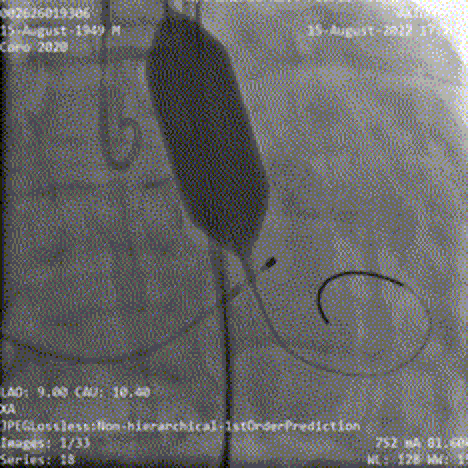

主动脉根部造影提示主动脉瓣重度反流,顺利完成跨瓣操作后予以23mm球囊充分预扩,提示无明显腰征,无造影剂渗漏,冠脉显影正常;

主动脉根部造影

球囊预扩